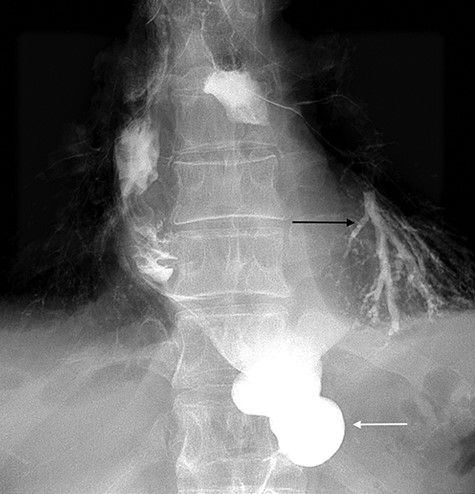

A 49-year-old male, with past medical history of tobacco smoking, who was diagnosed with adenocarcinoma of gastroesophageal junction underwent minimally invasive two-stage oesophagectomy. A month following discharge, he presented with complains of chest pain and persistent coughing (Ohno’s sign); barium swallow examination was conducted. This demonstrated a gastrobronchial fistula, between the newly formed gastric conduit and the left main bronchus (Figures 1 and 2). On endoscopic evaluation, a 5 mm communication between the tip of the gastric conduit and the left main bronchus with no evidence of ischemia and well-vascularised edges was noted.

Lateral view of barium swallow demonstrating gastrobronchial fistula.